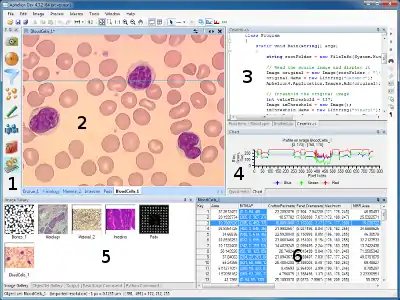

Aphelion Dev graphical user interface | |

Aphelion is widely used in the scientific/industry community to solve basic and complex imaging applications. First, the imaging application is quickly developed from the Graphical User Interface, involving a set of functions that can be automatically recorded into a macro command. The macro languages available in Aphelion (i.e. BasicScript, Python, and C#) help to process batch of images, and prompt the user if needed for specific parameters that are applied to the imaging functions. All Aphelion image processing functions are written in C++, and the Aphelion user interface is written in C#. C++ functions can be called from the C# language thanks the use of dedicated wrappers.[17]

- Aphelion Dev:[19] Full imaging environment including over 450 functions[20][21] to develop and deploy an application that involves image processing and analysis. It also includes a set of macro-command languages to automate any application to be invoked from the user interface. It also helps to run the imaging algorithm on more than one image that are stored on disk, available on the network, or captured by an acquisition device. Aphelion libraries for image processing and visualization are provided in Aphelion Dev as DLLs and .Net components.

The comprehensive set of Aphelion functions is used to analyze images coming from an optical microscope and a camera mounted on top of the microscope. The software also controls the automated stage mounted on the microscope in the X, Y and Z directions. Z is used to change focus. Measurements based on shape analysis (surface area, perimeter, volume, elongation, compactness, etc.) and texture analysis (e.g., homogeneity, average intensity, moments[48]) are automatically computed by Aphelion and displayed in the user interface in a spreadsheet on which statistical analysis as surface ratios[49] can be performed. Analysis reports can also be generated in the user interface and then saved in specific folders. Microscopes using reflected light can also be used for the analysis. For example, a specific software based on the Aphelion ActiveX components[34] is capable to measure inhibitor agent effects on dentin cells resorption.[50]

In the field of cytopathology, ADCIS developed a set of software products such as a specific software to analyze blood composition, count and classify red globules,[6] and another software to automatically classify cancerous cells using a classification based on multiple neural networks.[51][52] Images are first acquired by a video camera mounted on an automated optical microscope. They are then automatically processed by Aphelion, and cytoplasm and nuclei are segmented using a watershed algorithm. Aphelion has also been used to study tumor vascularization in low resolution images using a slide scanner (much cheaper than a scan microscope).[53] The software that was developed helped the detection of immune-marked cells.[28] Image analysis is also used in histology to study angiogenesis in 2D and 3D on microscopy images[54] to measure effects of inhibitors and accelerants impact on blood vessels growth.